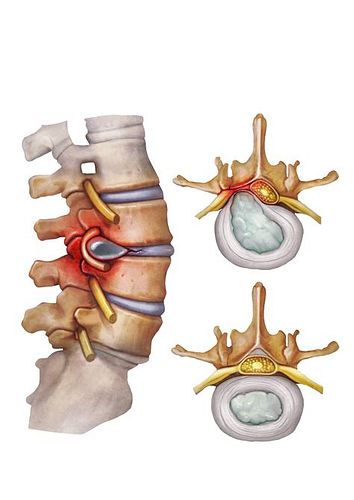

디스크(disc)는 척추뼈와 척추뼈 사이에 위치한 젤리 같은 물렁뼈 조직으로, 우리말로는 추간판이라고 부릅니다. 이 조직은 척추뼈끼리 직접 부딪히는 것을 막아주는 쿠션 역할을 하며, 척추의 움직임을 부드럽게 하고 외부 충격을 흡수하는 기능을 담당합니다.

디스크의 구조는 다음과 같습니다:

- 수핵: 중심부에 위치하며, 젤리처럼 말랑말랑하고 수분이 많아 충격을 흡수합니다.

- 섬유륜: 수핵을 둘러싸는 질긴 막으로, 수핵이 밖으로 빠져나가지 않도록 보호합니다.

디스크에 과도한 힘이 가해지거나 노화 등으로 인해 섬유륜이 손상되면, 내부의 수핵이 밖으로 튀어나올 수 있습니다. 이때 튀어나온 수핵이 신경을 압박하여 통증이나 감각 이상, 심하면 마비 증상까지 유발할 수 있는데, 이를 흔히 **허리디스크(요추 추간판 탈출증)**라고 부릅니다.